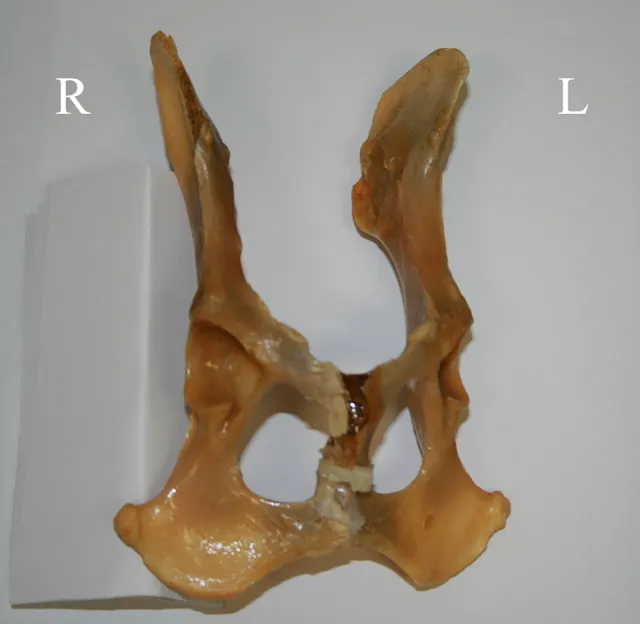

Figure 1A demonstrates the normal positioning for the ventrodorsal hip-extended view (the view that should be submitted to the Orthopedic Foundation for Animals). This view is best obtained with the dog placed in dorsal recumbency, which is done by using a foam positioning trough. All but the pelvis and hindlimbs are within the trough. While in a flexed position, the limbs are internally rotated and abducted so that the stifles are almost touching. The limbs are then extended, maintaining the internal rotation, until the femurs are parallel with the table.

If the stifles are kept internally rotated, the patella should be centrally located over the distal femurs, as seen in the normally positioned radiograph (Figure 1B). In this image the femurs are parallel with each other and parallel with the imaging plate. Note the uniform and equal size of the obturator foramen on this well-positioned radiograph. Ideally, the sacrum, ilial wings, and entire 7th lumbar vertebra should be included in the image. Figure 1C shows an example of the pelvis correctly positioned.